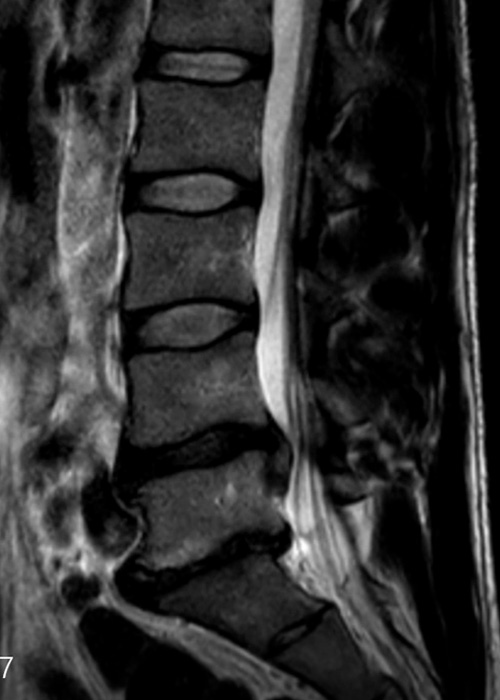

Tras realizar las pruebas de diagnóstico pertinentes y proceder a una exhaustiva exploración, se le diagnostica una hernia discal de gran tamaño entre la 4ª y la 5ª vértebra lumbar, que ocupa prácticamente todo el canal y comprime las raíces y tejido neurológico que se alojan en la columna.